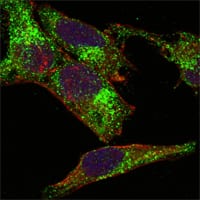

分类: 科研抗体货号: 20125别名: ARG; ABLL; FLJ22224; FLJ31718; FLJ41441应用: IF反应种属: Human